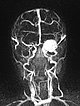

Dynamische, kontrastmittelunterstützte MR-Angiographie des Schädels und der hirnversorgenden Gefäße. In der ganz früharteriellen Phase (A) noch kein Enhancement der Läsion am linken Auge.